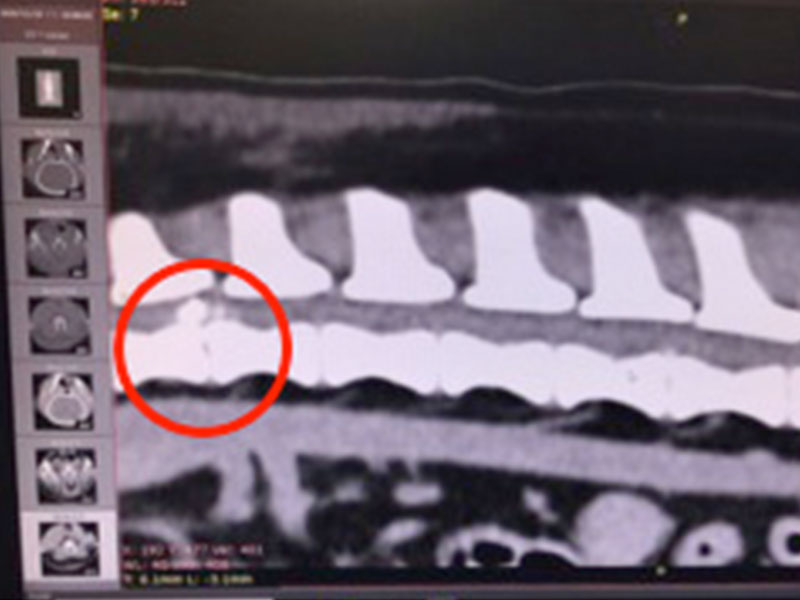

臘腸狗狗好發的椎間盤疾病 IVDD 第四級 脊椎外科手術 電腦斷層

• ​IVDD 狗狗的椎間盤疾病 4級癱瘓

​IVDD 狗狗的椎間盤疾病 4級癱瘓